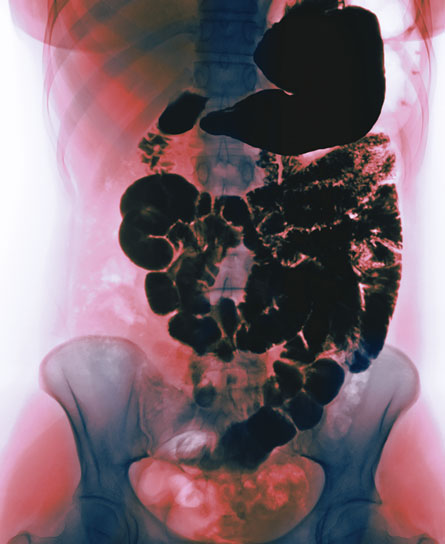

It’s easy to perceive bones as dense and dead. But on the inside, bones are not hard like blocks of wood, but airy, like sponges. The internal, honeycomb-like scaffolding allows bones to be sturdy without leaving them too heavy. Strength isn’t determined by density but by the makeup of the matrix within (in the same way a china plate is denser than a plastic one but less likely to survive a drop on the floor).